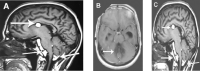

Dermoid cysts are rare, benign lesions of embryological origin that represent 0.1-0.7% of all intracranial tumors. They are mainly located in the supra tentorial space, especially in the parasellar region. Their location in the posterior fossa remains uncommon. Rupture of intracranial dermoid cysts is a rare phenomenon. We present a case of dermoid cyst, which had ruptured into ventricular system. Computed Tomography and MRI revealed fat in the fourth ventricle, prepontine cistern, and cerebellomedullary cistern. Hydrocephalus was noted. We performed right ventriculo-peritoneal shunt on which patient improved and he continues to remain asymptomatic one year after.